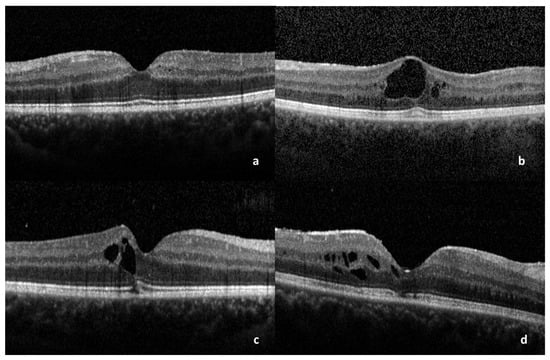

3. Results